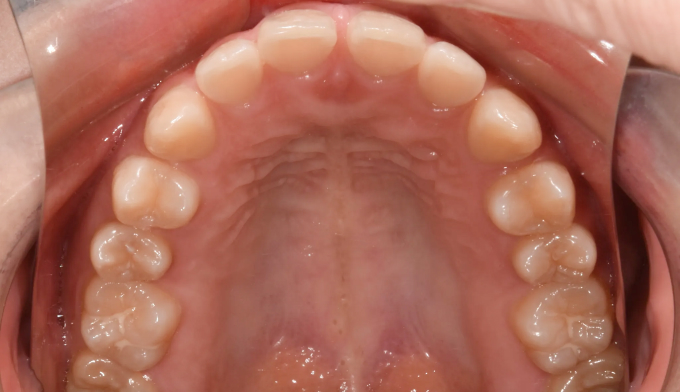

아래 앞니 하나가 선천적으로 부족한 경우이지만 주걱턱 경향으로 인해 아랫니가 윗니를 계속 자극하여 윗니까지 벌어진 케이스입니다. 윗니의 공간을 닫아주기 위하여 아래앞니를 먼저 후방이동시켜줬고, 이후에 벌어진 윗 앞니를 가지런하게 모아 마무리하였습니다. 아래앞니 하나가 부족하기때문에 위아래 가운데선을 맞추지 않고 종료하였습니다. 총 교정기간은 11개월입니다.